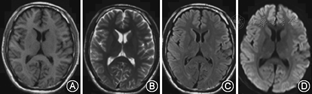

例1、例3均未给予特殊治疗;例1给予80 mg/d甲泼尼龙冲击治疗1周;例4给予抗感染、改善肾功能、纠正贫血治疗;患者临床症状均在1~2周内明显改善。分别于发病后32、7、5、8 d后复查头颅MRI,例1、2、4病灶完全消失(图3,图4)。例3胼胝体压部病变范围减小且异常信号强度减弱。

MRI显示胼胝体压部的孤立性异常信号和病灶的可逆性消失是本病主要的诊断依据。Takanashi等[7,8]根据MRI特点将MRES其分为Ⅰ型和Ⅱ型,即病灶局限于胼胝体压部的Ⅰ型和同时累及深部白质或皮质下白质的Ⅱ。本组3例患者MRI表现为胼胝体压部的孤立的类圆形病变,符合MRES分型Ⅰ型;1例表现为整个胼胝体压部受累的弧形病变,类似于"回旋镖征"[9],同时累及胼胝体外,符合Ⅱ型。Takanashi等[7]发现MRES Ⅱ型可向Ⅰ型转变,胼胝体外的异常信号可先于胼胝体压部的异常信号消失。本组1例患者MRI上DWI仅见胼胝体压部异常信号,而T2WI、FLAIR显示胼胝体及胼胝体外异常信号,推测这种不匹配的其可能的原因是患者行MRI检查是处于Ⅱ型向Ⅰ型转换的中间阶段,胼胝体外病变正逐渐消失,DWI较T2WI及FLAIR能够更敏感的显示这种改变。本研究Ⅰ型和Ⅱ型患者的临床症状及预后方面无差异,与Takanashi等[8]的报道一致。也有研究发现,胼胝体外病变的出现可能提示预后不良[10]。本组4例患者MRI病变在首次行MRI检查后4~17 d消失,患者临床症状的完全恢复晚于MRI病灶的消失。